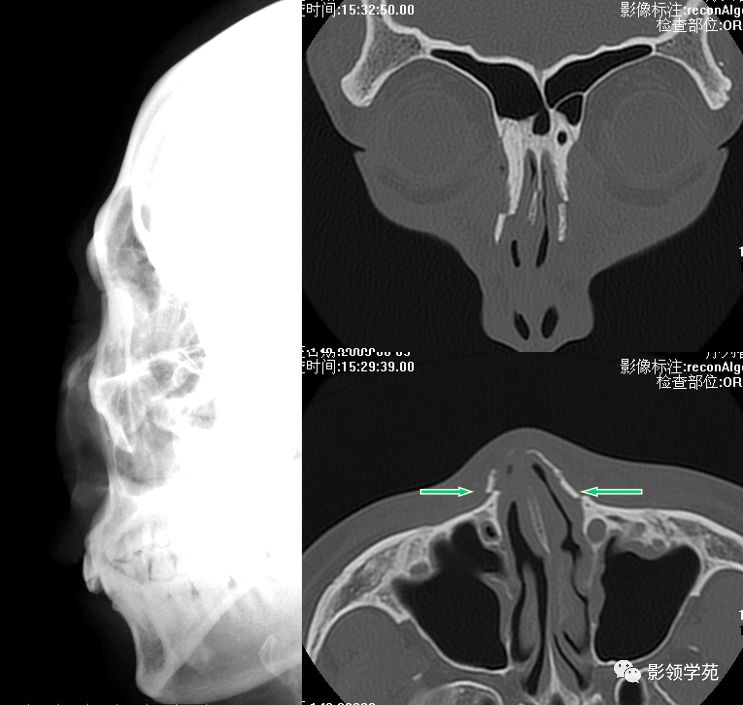

X线平片:侧位

HRCT

- 横断面:听眶下线

- 冠状面:鼻骨长轴平行线

- 层厚:1~2mm

鼻骨正常侧位

鼻骨横断面HRCT

鼻骨冠状面HRCT

线性骨折 粉碎骨折

右侧鼻骨线形骨折

鼻骨线形骨折

左侧鼻骨线形骨折

右侧鼻骨骨折

左上颌骨额突骨折

双侧鼻骨骨折

双侧上颌骨额突骨折

鼻中隔骨折